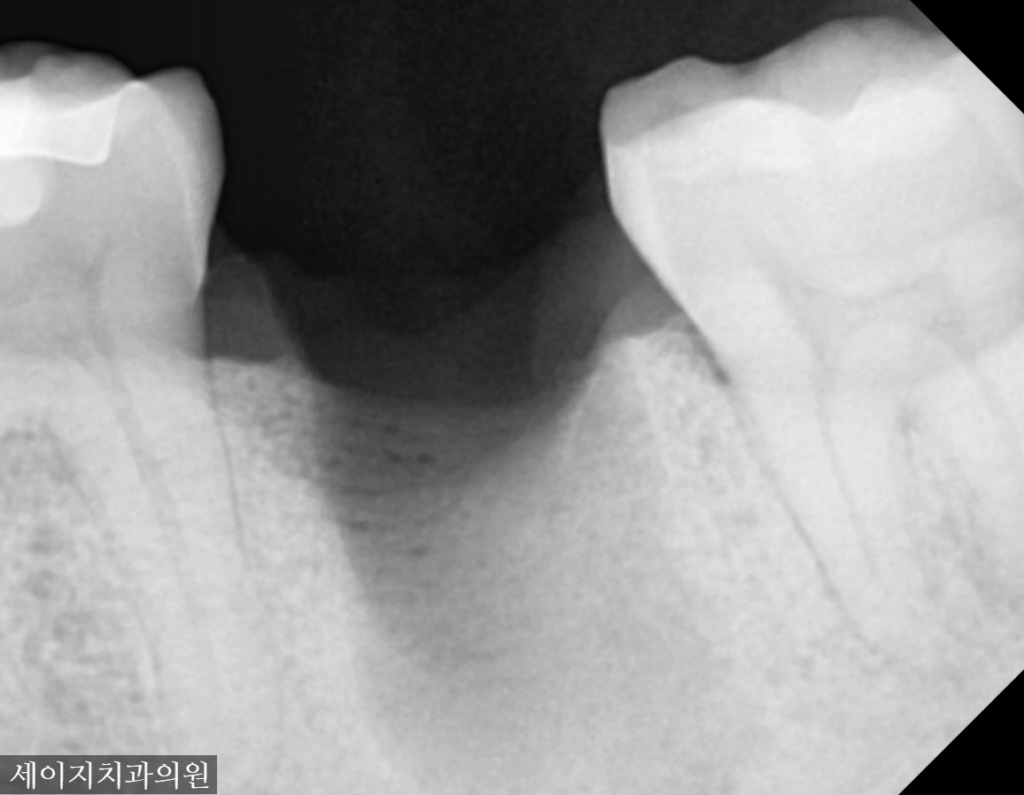

먼저 X-ray 장비를 이용하여 해당부위를 관찰하였습니다. 예상대로, 치아의 뿌리쪽에 염증이 생겨 있었으며 광범위한 상태의 골소실이 관찰되었습니다.

사진 설명을 입력하세요. 해당치아는 광범위한 골소실로 인해 발치로 치료계획을 설정하였습니다. 3D CT 장비를 이용하여 해당 부위의 골조직의 염증 부위를 확인하고 정확한 식립을 위해 모의 수술을 해보았습니다.